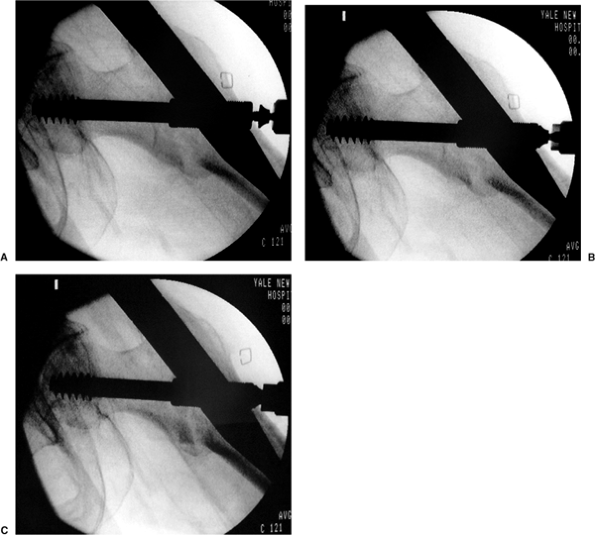

sliding adjunct). Once the lag screw has reached the appropriate depth (Fig. 17.17A)

and the reduction is verified, the centering sleeve should be advanced

though the lateral cortex and into the nail using the sleeve pusher (Fig. 17.17B).

the screw is seated into the dense subchondral bone. On right hips,

screw insertion tends to extend the fragment, which often helps correct

mild extension deformities at the fracture. However, for left-side

fractures, the clockwise seating of the screw flexes the hip and

worsens any extension deformity at the fracture. We scrutinize the

fracture on the lateral fluoroscopic image while slightly rotating the

screw insertion wrench back and forth (which controls the head-neck

fragment) to identify the optimum reduction (Fig. 17.18). The reduced position is then maintained while the AP image is obtained to confirm the reduction. The sleeve is then

locked to the nail when we tighten the previously inserted set screw with the torque-limited driver (Fig. 17.19). This locks in the rotational reduction but allows unimpeded sliding of the screw in the sleeve.

Figure 17.18. A. Lag screw insertion in a left hip showing worsening of extension deformity. B. Rotation of the screw results in fracture reduction.

|